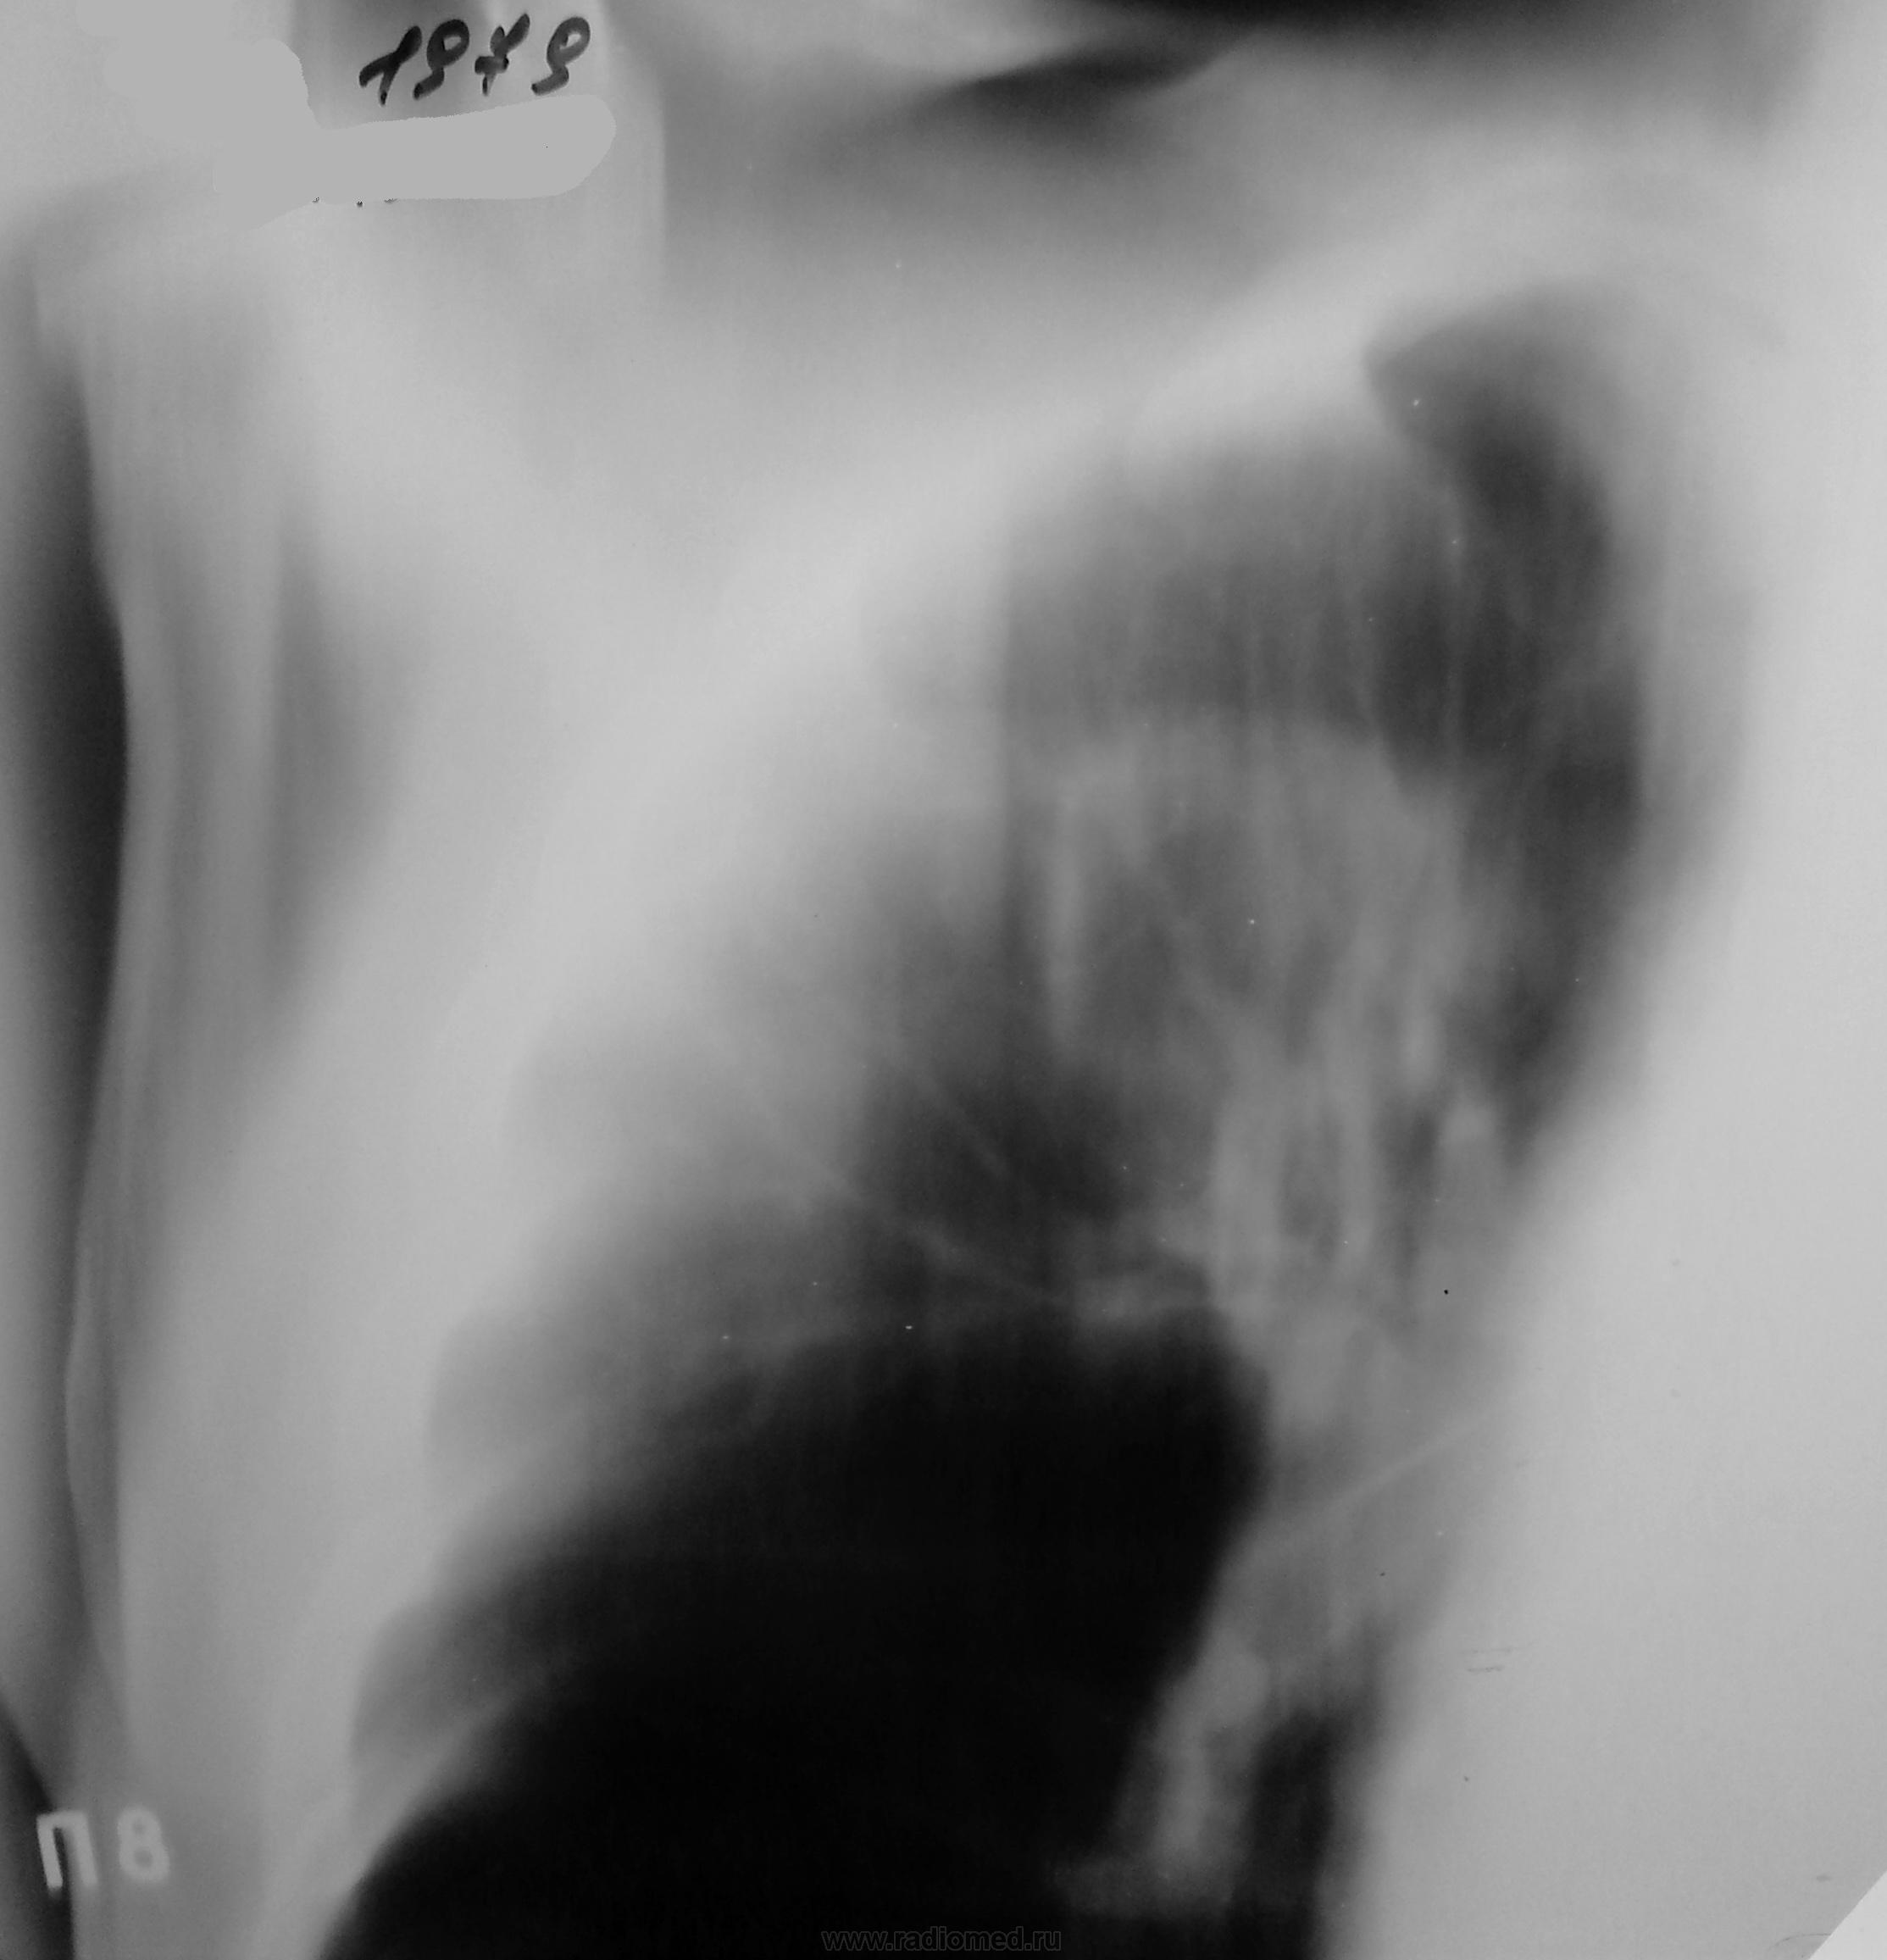

А, вот правый боковой (нам старичкам) очень помог бы...

Кольцевидная тень верхней доли правого легкого с неравномерной стенкой, наибольшей по толщине с "1 по 3 ч", полостью распада с неровным достаточно ясным контуром. Секвестров не отмечено. Внешний контур также ясный (термин, невилирующий разницу между "размытый" и "четкий"). Видны перифокальные очаги мелких и средних размеров ниже и медиальнее "кольца". Перибронхиальная инфильтрация прилежащих бронхов. В дифф.ряд поставил бы всё выше указанное с акцентом на инф.туб. с распадом.

боковой где-то затерялся. к сожалению, представить не могу. но как придет на контроль - сделаем. если фтизиатры не заберут..